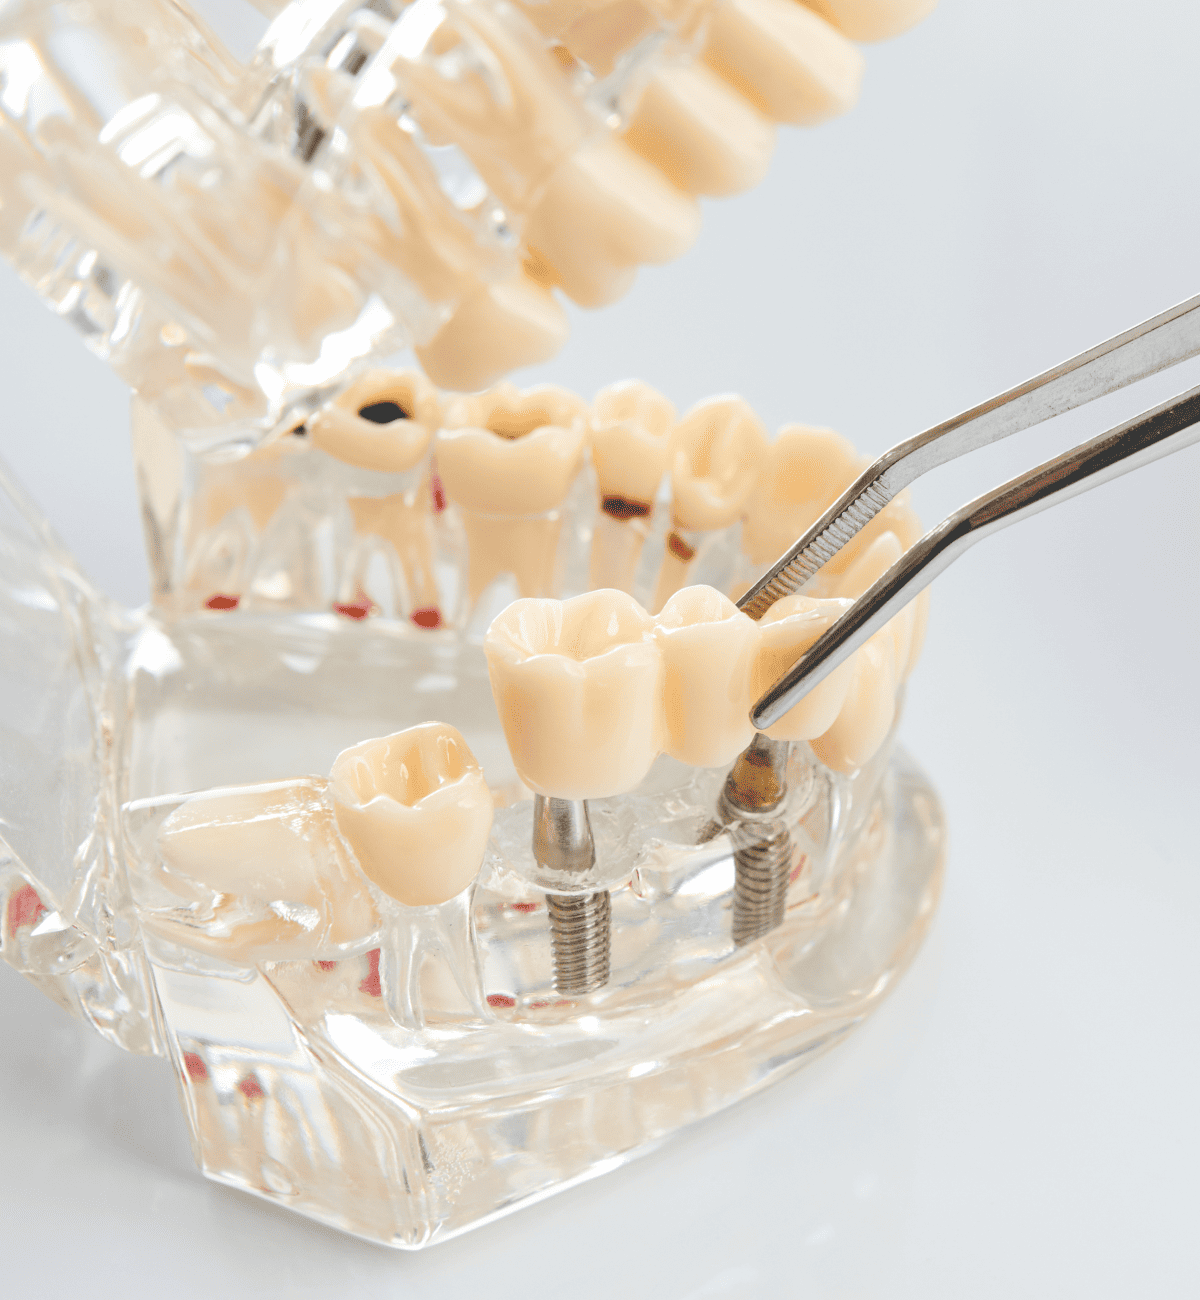

代表的な再生療法のひとつが「GBR(骨誘導再生法)」です。骨が不足した部位に自家骨や人工骨を補填し、特殊な膜(メンブレン)で覆うことで、骨の再生を促しインプラントの土台を築く方法です。

また、上顎奥歯など骨が特に薄い部位には「サイナスリフト(上顎洞底挙上術)」が適応されます。上顎洞と呼ばれる空洞の底を持ち上げ、その下に骨を造成することで、十分なインプラント埋入スペースを確保することが可能になります。

これらの高度な再生治療は、歯科用CTや精密シミュレーション技術、そして確かな経験を持つ術者による対応が前提となります。